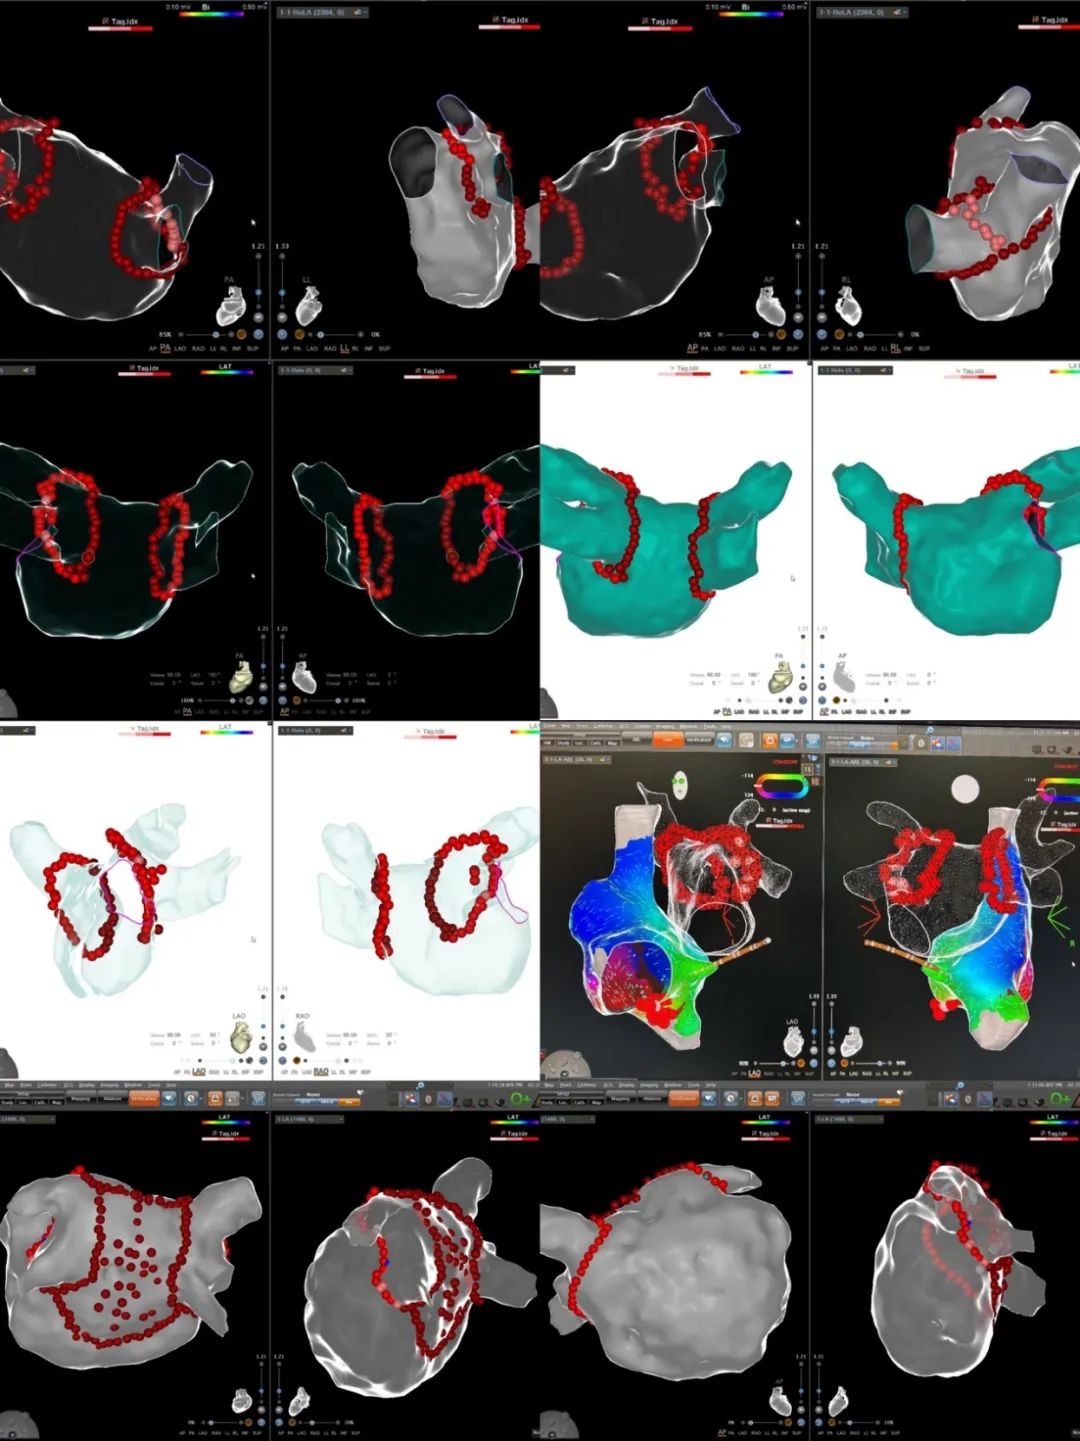

在此次直播中,多位知名专家展示了超过20例在QDOT智能温控超高功率消融导管指导下进行的射频消融手术。手术过程中,专家们的精湛操作与创新的QDOT导管相结合,使与会者更直观地感受到该技术在临床应用中的优势。同时,24场前沿讨论也同步举行,专家们围绕超高效消融结合稳定贴靠技术、超高效消融结合超声技术以及超高效消融结合低零射线技术等主题,深入分析了QDOT的实际应用,分享了他们丰富的临床经验,为消融治疗开辟了新的思路和方向:

QDOT MICRO一次性使用压力监测射频消融导管是强生医疗科技推出的射频消融导管领域的集大成者。它能够通过实时温度反馈,智能自适应调节功率和盐水灌注。导管配备了6个温度感受器,不仅提升了温度感知灵敏度,还能有效降低并发症发生率,让医生在手术过程中更加安心地进行高效消融操作。此外,新增的3个微电极可助力诊断复杂心律失常中的特殊电位,为精准治疗提供有力支持。

此外,QDOT MICRO导管将盐水灌注孔增加到66个,大大提高了灌注效率,降低了心脏负荷,尤其适用于心衰患者的房颤消融,为这类高难度手术提供了更安全有效的解决方案。值得一提的是,作为目前全球首款双消融模式压力导管,QDOT可在QMODE和QMODE+模式(90W/4S)之间随心切换,显著提高手术效率,将手术时间缩短 36%。